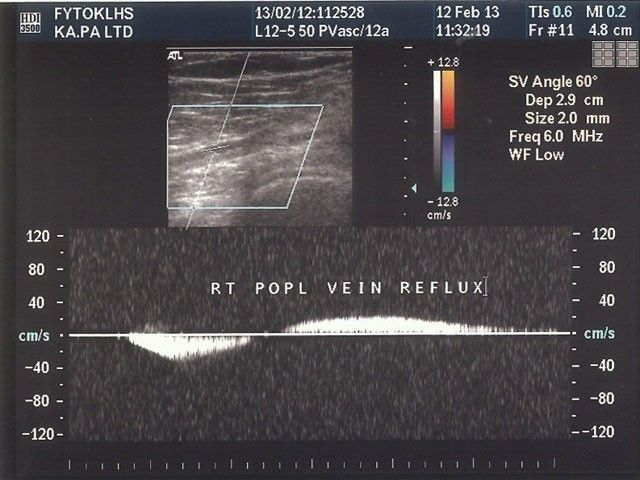

Η Φλεβική Ανεπάρκεια στο επιφανειακό ή στο εν τω βάθει φλεβικό δίκτυο διαγιγνώσκεται με τη βοήθεια των υπερήχων (Triplex). Συνήθως οι ασθενείς παραπονούνται για οιδήματα στα κάτω άκρα, πόνους, κράμπες, κνησμό και βαριά πόδια, σε συνδυασμό με αλλαγή του χρώματος του δέρματος και, ενίοτε, με φλεβικά έλκη.

Φλεβική Θρόμβωση μπορεί να συμβεί είτε στο επιφανειακό είτε στο εν τω βάθει φλεβικό δίκτυο. Ο βασικός κίνδυνος είναι η πνευμονική εμβολή, δια τούτο και απαιτείται ταχεία διάγνωση, συνήθως με τη βοήθεια των υπερήχων (Triplex) και έγκαιρη θεραπευτική αντιμετώπιση, συνήθως με αντιπηκτικά. Ο ασθενής, σε ορισμένες περιπτώσεις, διερευνάται για ύπαρξη θρομβοφιλίας.